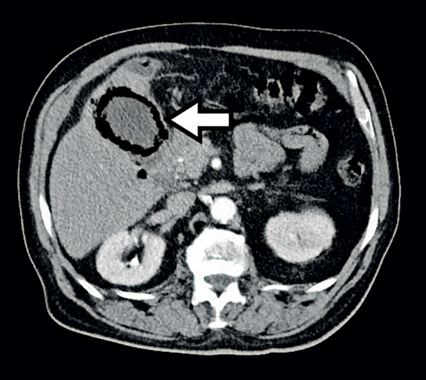

Se presenta el caso de un hombre de 84 años, con antecedentes de hipertensión arterial controlada y enfermedad pulmonar obstructiva crónica, quien consultó por dolor tipo cólico en el hemiabdomen superior, exacerbado por la ingesta de alimentos, irradiado al área periumbilical. Al examen físico había dolor en el hipocondrio derecho, masa palpable y signo de Murphy positivo. Los paraclínicos mostraron leucocitosis leve y transaminasas discretamente elevadas. La ecografía no identificó la vesícula biliar, por lo que se realizó una tomografía computarizada que mostró gas en la pared vesicular y el segmento V del hígado (Figura 1), sugiriendo colecistitis enfisematosa con posible ruptura. Durante la cirugía laparoscópica se identificó un plastrón inflamatorio, por lo que se optó por convertir a cirugía vía abierta; así se encontró una perforación en el tercio inferior de la vesícula y contenido fibrinopurulento (Figura 2). El paciente evolucionó favorablemente, recibiendo alta tras seis días. El análisis histopatológico confirmó inflamación severa, necrosis focal y hemorragia reciente en la pared vesicular (Figura 3).